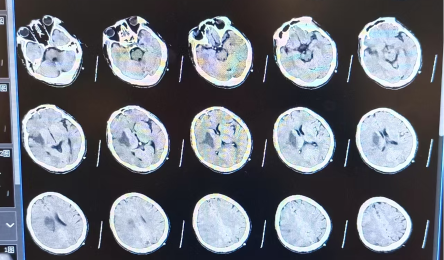

5月底一个普通的夜晚,34岁的工程师王某(化名)突然倒下了。他的左侧身体动弹不得,话也说不清楚——这是凶险的急性脑中风(脑梗死)的信号!家人立刻将他送往通用环球西安北环医院,一场惊心...